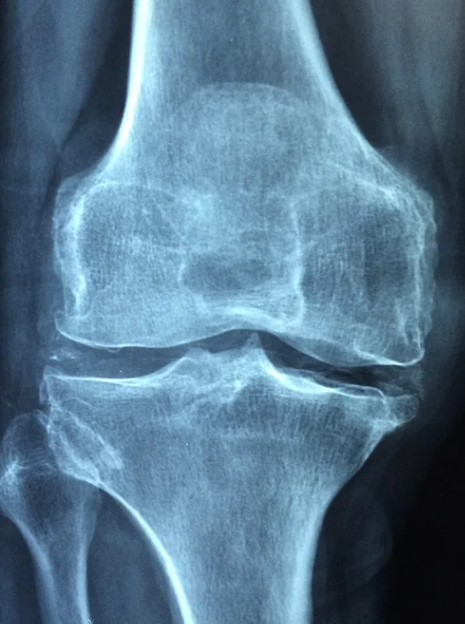

우리 몸에서 가장 많은 움직임이 있는 곳 중 하나가 바로 무릎일 것이다. 그만큼 무릎에 통증이 생긴다는 것은 곧 움직임에 제한이 생긴다는 것이고 연골에 그만큼 손상이 있다는 것이라고 짐작해볼 수 있다.

무릎 연골이라는 것은 한번 손상되기 시작하면 자연적으로 치유되지 않고, 계속 방치하게 되면 손상 부위가 점점 커지게 되어서 퇴행성 관절염을 앞당기게 되는 원인이 된다.

무릎 관절에 어떤 이유가 되었든 부담을 주게 되면 연골을 손상시켜서 무릎 관절염을 발생시키기도 한다.

무릎 연골 관절에는 허벅지뼈와 정강이뼈가 맞닿아있다고 한다. 이들의 뼈 끝에 있는 골연골은 뼈가 서로 부딪히면서 손상이 되지 않도록 하는 역할을 하게 되는데, 우리가 무릎에 무리를 줄 수 있는 행동이나 운동을 반복하게되면 뼈를 감싸고 있는 연골이 손상되기 때문에 평소에 무릎이 자주 아프다면 아래에서 언급하는 무릎 연골 손상 대표적 증상 TOP 6에 대해서 알아보고 자신이 해당하는지 파악해보기 바란다.